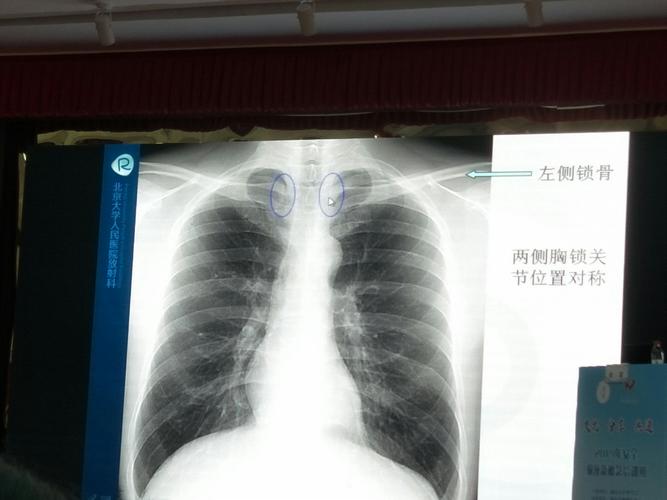

以影识病丨患者胸片异常可能的疾病是